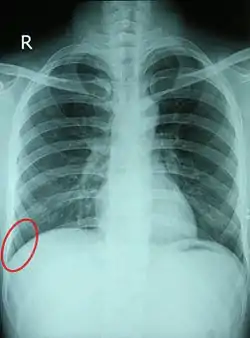

![]() Chest X-ray of a 30-year-old healthy man, with the costodiaphragmatic recess label in red ellipse | |

The costodiaphragmatic recess, also called the costophrenic recess or phrenicocostal sinus,[1] is the posterolateral fringe of the pleural space, a potential space around the lung inside the pleural cavity. It is located at the acutely angled junction ("reflection") between the costal and diaphragmatic pleurae, and is interpreted two-dimensionally on plain X-rays as the costophrenic angle. It measures approximately 5 cm (2.0 in) vertically and extends from the eighth to the tenth rib along the mid-axillary line.

Each costophrenic angle can normally be seen as on chest x-ray as a sharply-pointed, downward indentation (dark) between each hemi-diaphragm (white) and the adjacent chest wall (white). A small portion of each lung normally reaches into the costophrenic angle. The normal angle usually measures thirty degrees.